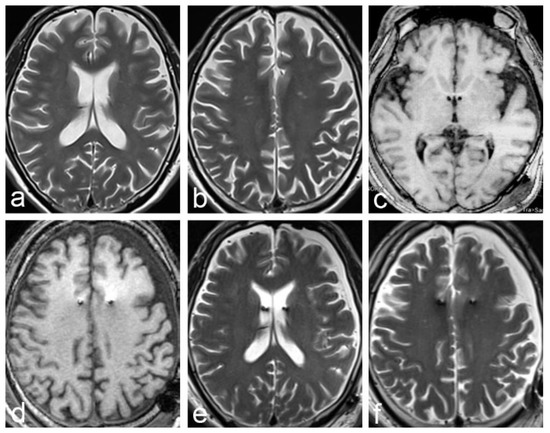

2.1. Case 1

2.2. Case 2

| Case 1 | 62 | F | Parkison’s disease | GPI | Yes | Yes | 36 days | description | poor |

| Case 2 | 56 | M | Alzheimer’s disease | fornix | Yes | Yes | 49 days | description | poor |